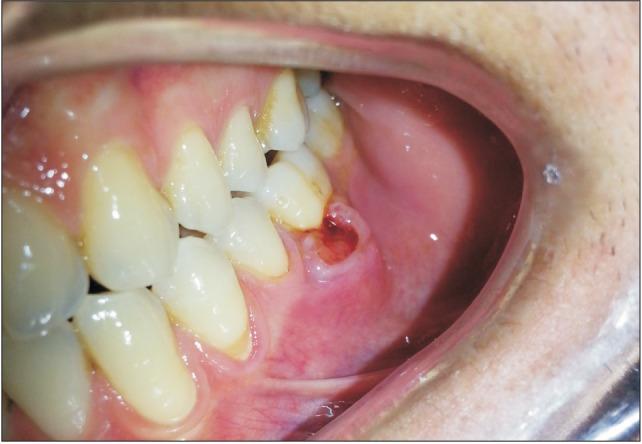

Leiomyoma is a type of benign smooth muscle neoplasm that is a common neoplasm of the uterus and gastrointestinal tract but rarely affects the head and neck region and is especially unlikely to affect the oral cavity. The diagnosis of leiomyoma is mainly determined by histopathological studies due to variation in its clinical appearance and symptoms. In the present paper we report two rare cases of gingival angioleiomyoma in the posterior maxilla and mandible. After total excision, hematoxylin-eosin and smooth muscle actin staining confirmed the diagnosis of angioleimyoma.